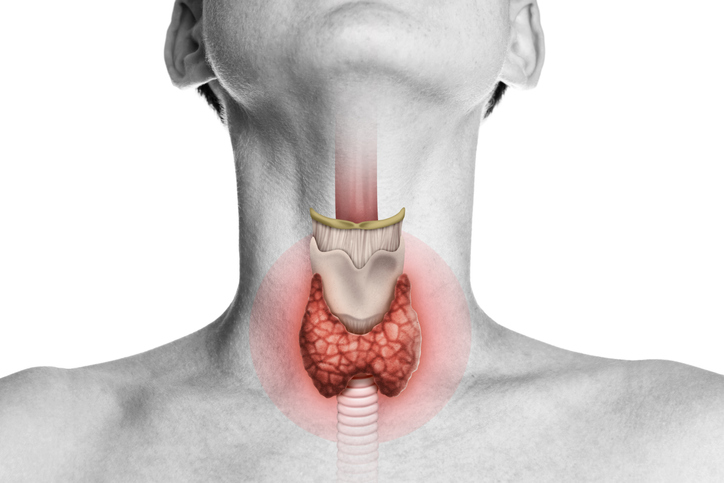

Impacto del COVID sobre la tiroides

¿Cuál es el impacto del COVID sobre la tiroides? Oded Stempa responde las dudas que tienen cuentahabientes. Después de la gripe española, el Covid 19, es la pandemia más letal y de más rápida propagación de la que se tenga registro. Alrededor de 6,3 millones de personas han muerto a nivel mundial a consecuencia de la […]

Oda a la tiroides

Les vamos a dar unas clases infernales sobre la tiroides, qué es, cuál es su función y tooodos los tipos de enfermedades que vienen de ella.

¿Qué onda con los nódulos tiroideos?

Les vamos a dar clases de tiroides, para qué sirven, qué hacen en nuestro cuerpo, y qué onda con los nódulos, qué son y cuándo debemos preocuparnos.

Tiroides: hipotiroidismo e hipertiroidismo

Les vamos a dar una clase INFERNAL sobre tiroides: Cuál es su función, cómo lo hace y qué regula en el cuerpo.